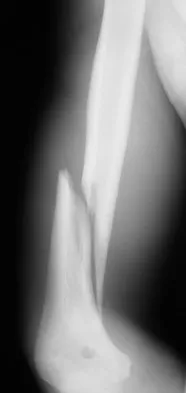

A 25-year-old patient who sustained multiple bilateral rib fractures, a pulmonary contusion, a left nondisplaced transtectal acetabular fracture, and a closed humerus fracture in a motor vehicle accident 2 weeks ago is transferred from another hospital. The humerus fracture has been surgically treated. There are no signs of infection, and the trauma surgeon wants to mobilize the patient as soon as possible. Radiographs are shown in Figures 15a and 15b. Management of the humerus fracture should consist of